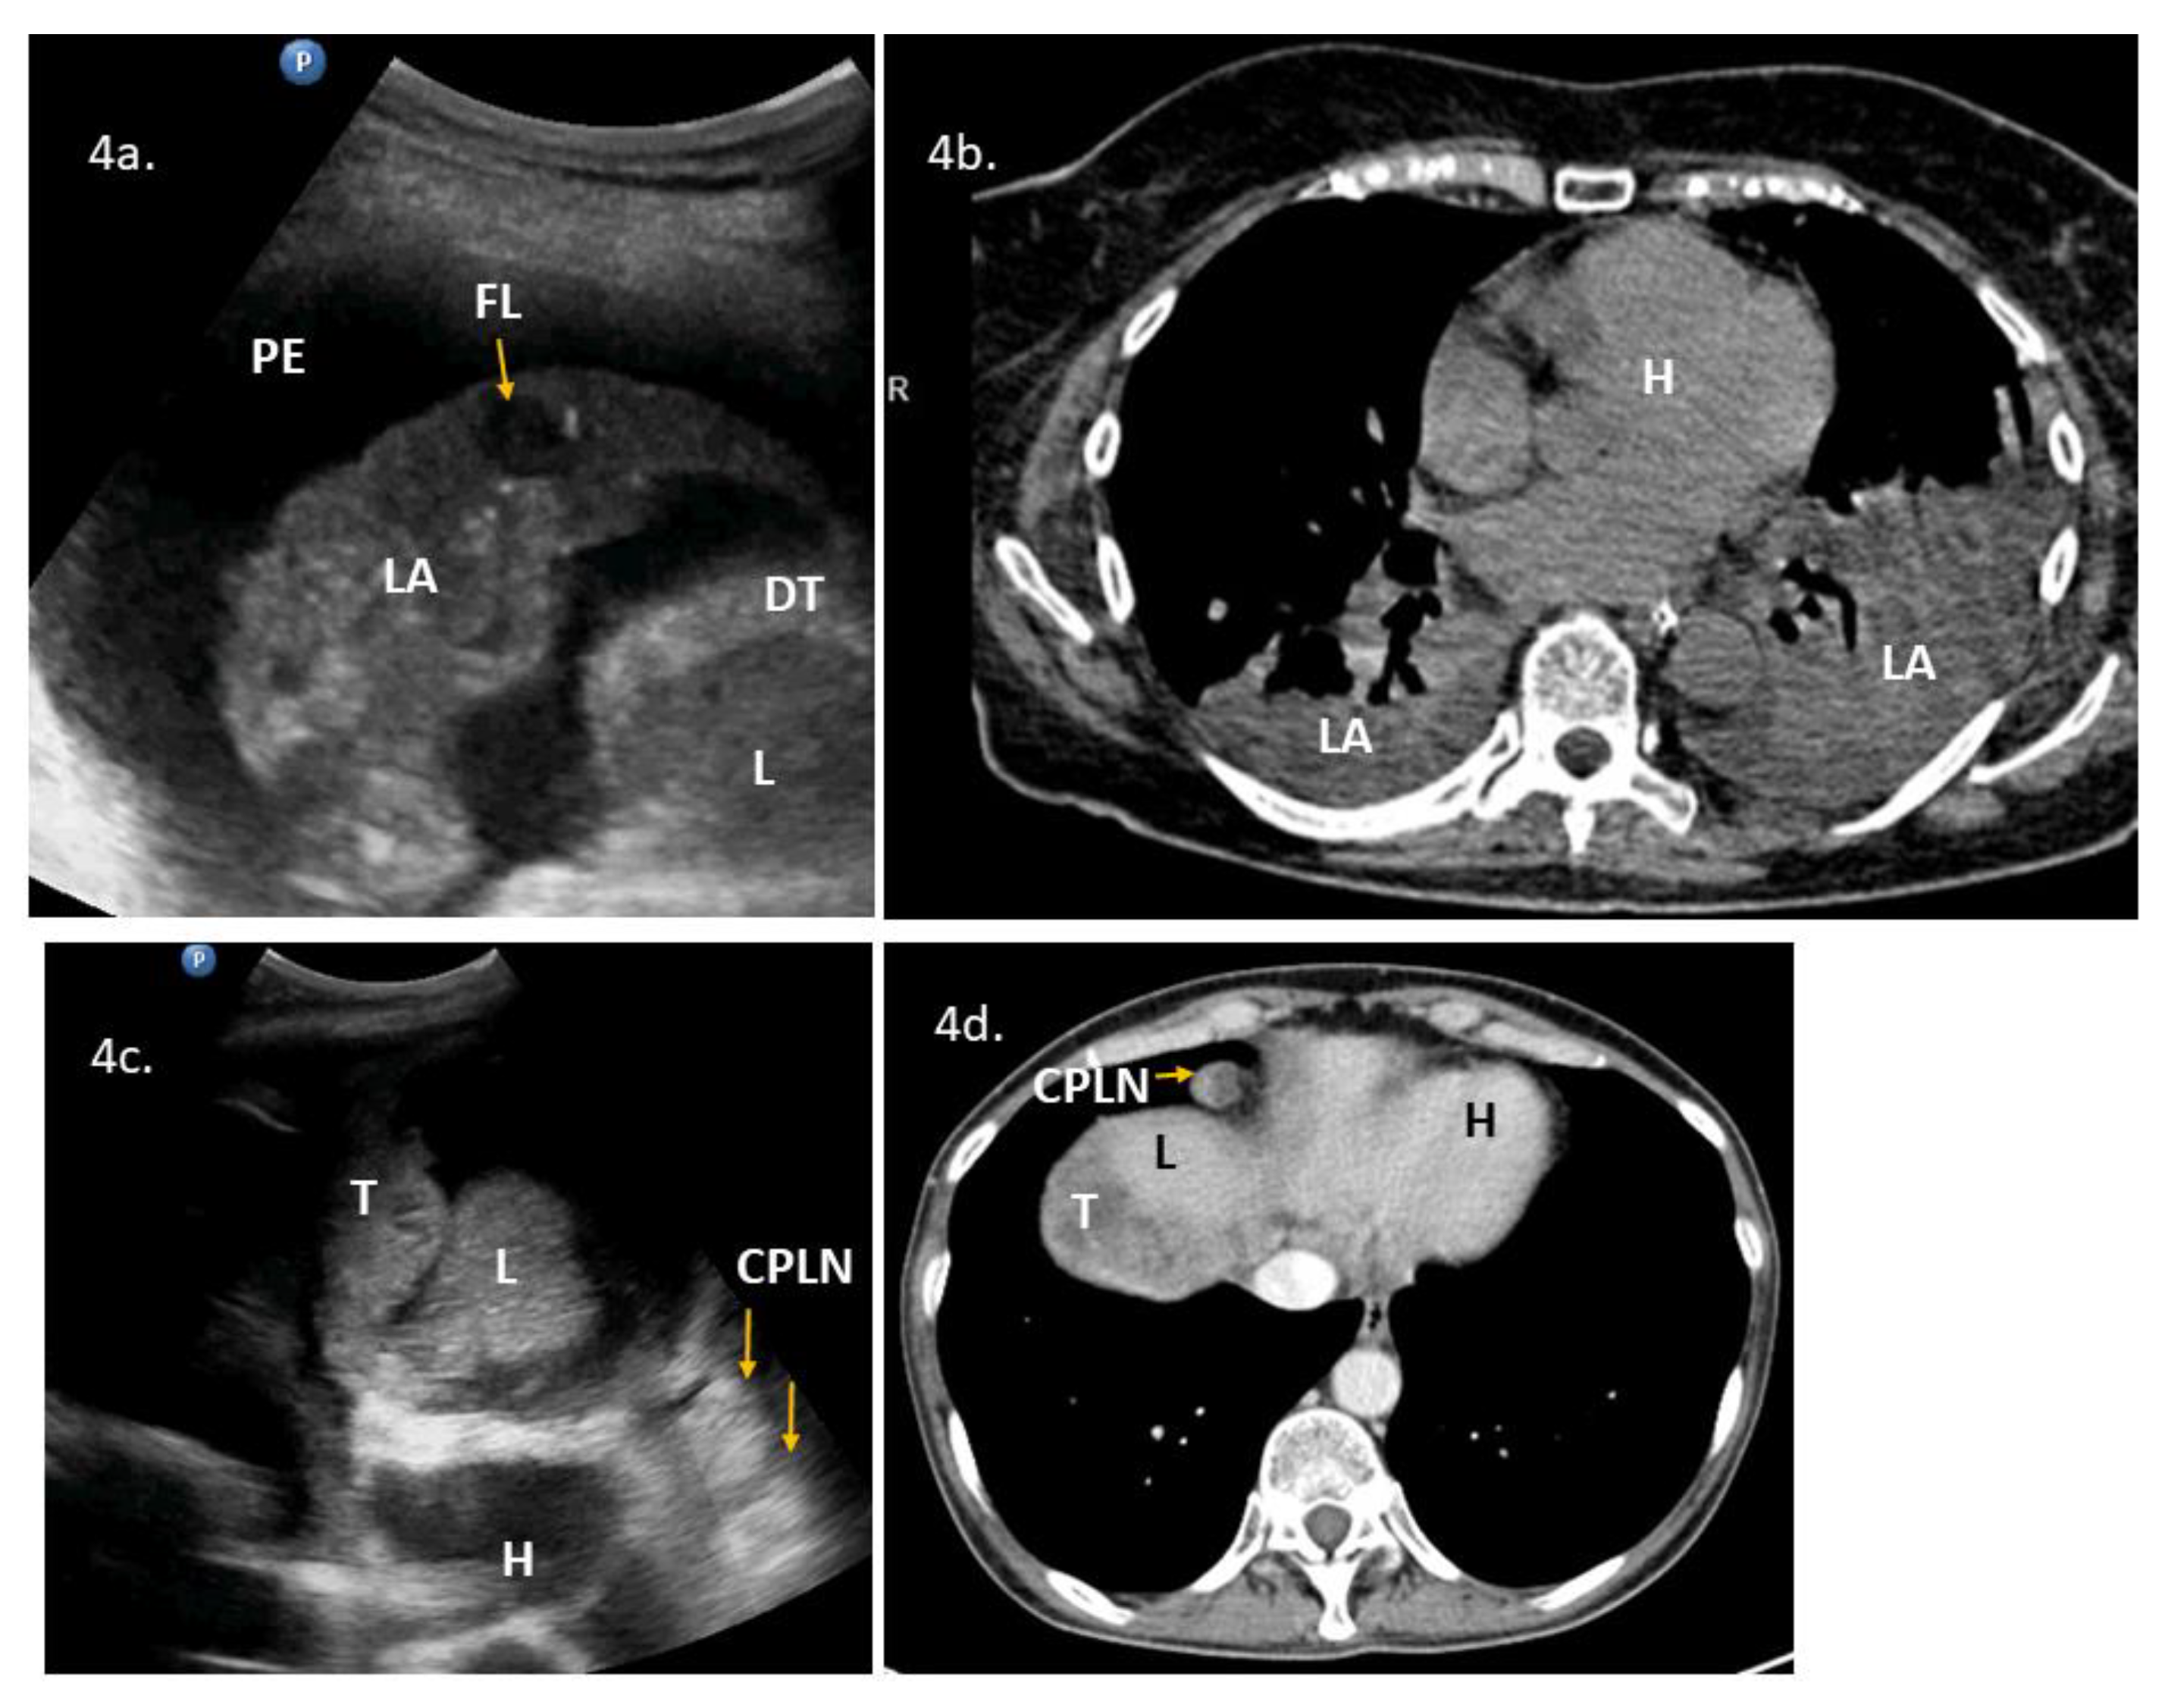

| 8 | 74 | 3 | ascites, carcinomatosis, massive pelvic involvement, omental involvement | pleural diaphragm involvement *, lung parenchymal pathology, pleural effusions | ascites, carcinomatosis, massive pelvic involvement, omental involvement, pleural effusions, other | Yes | Yes | YesScore: 7 → 9 Intermediate → High | No | 4a, 4b, VS8 | DLSK, HGSOC. NACT. |